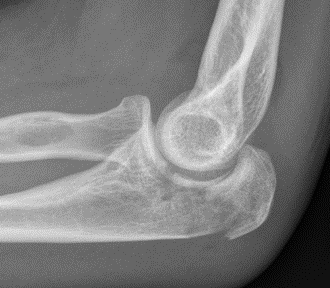

Proximal articular portion of the ulna

- greater sigmoid notch articulates with trochlea

- has a central bare area

- flexion / extension

Triceps insertion

- attaches to olecranon

- displaces olecranon fragment superiorly

Mayo Classification

A: Non comminuted

B: Comminuted

| Type I | Type II | Type III |

|---|---|---|

| Minimally displaced | Displaced | Trans-olecranon fracture dislocation |

| 10% | 85% | 5% |